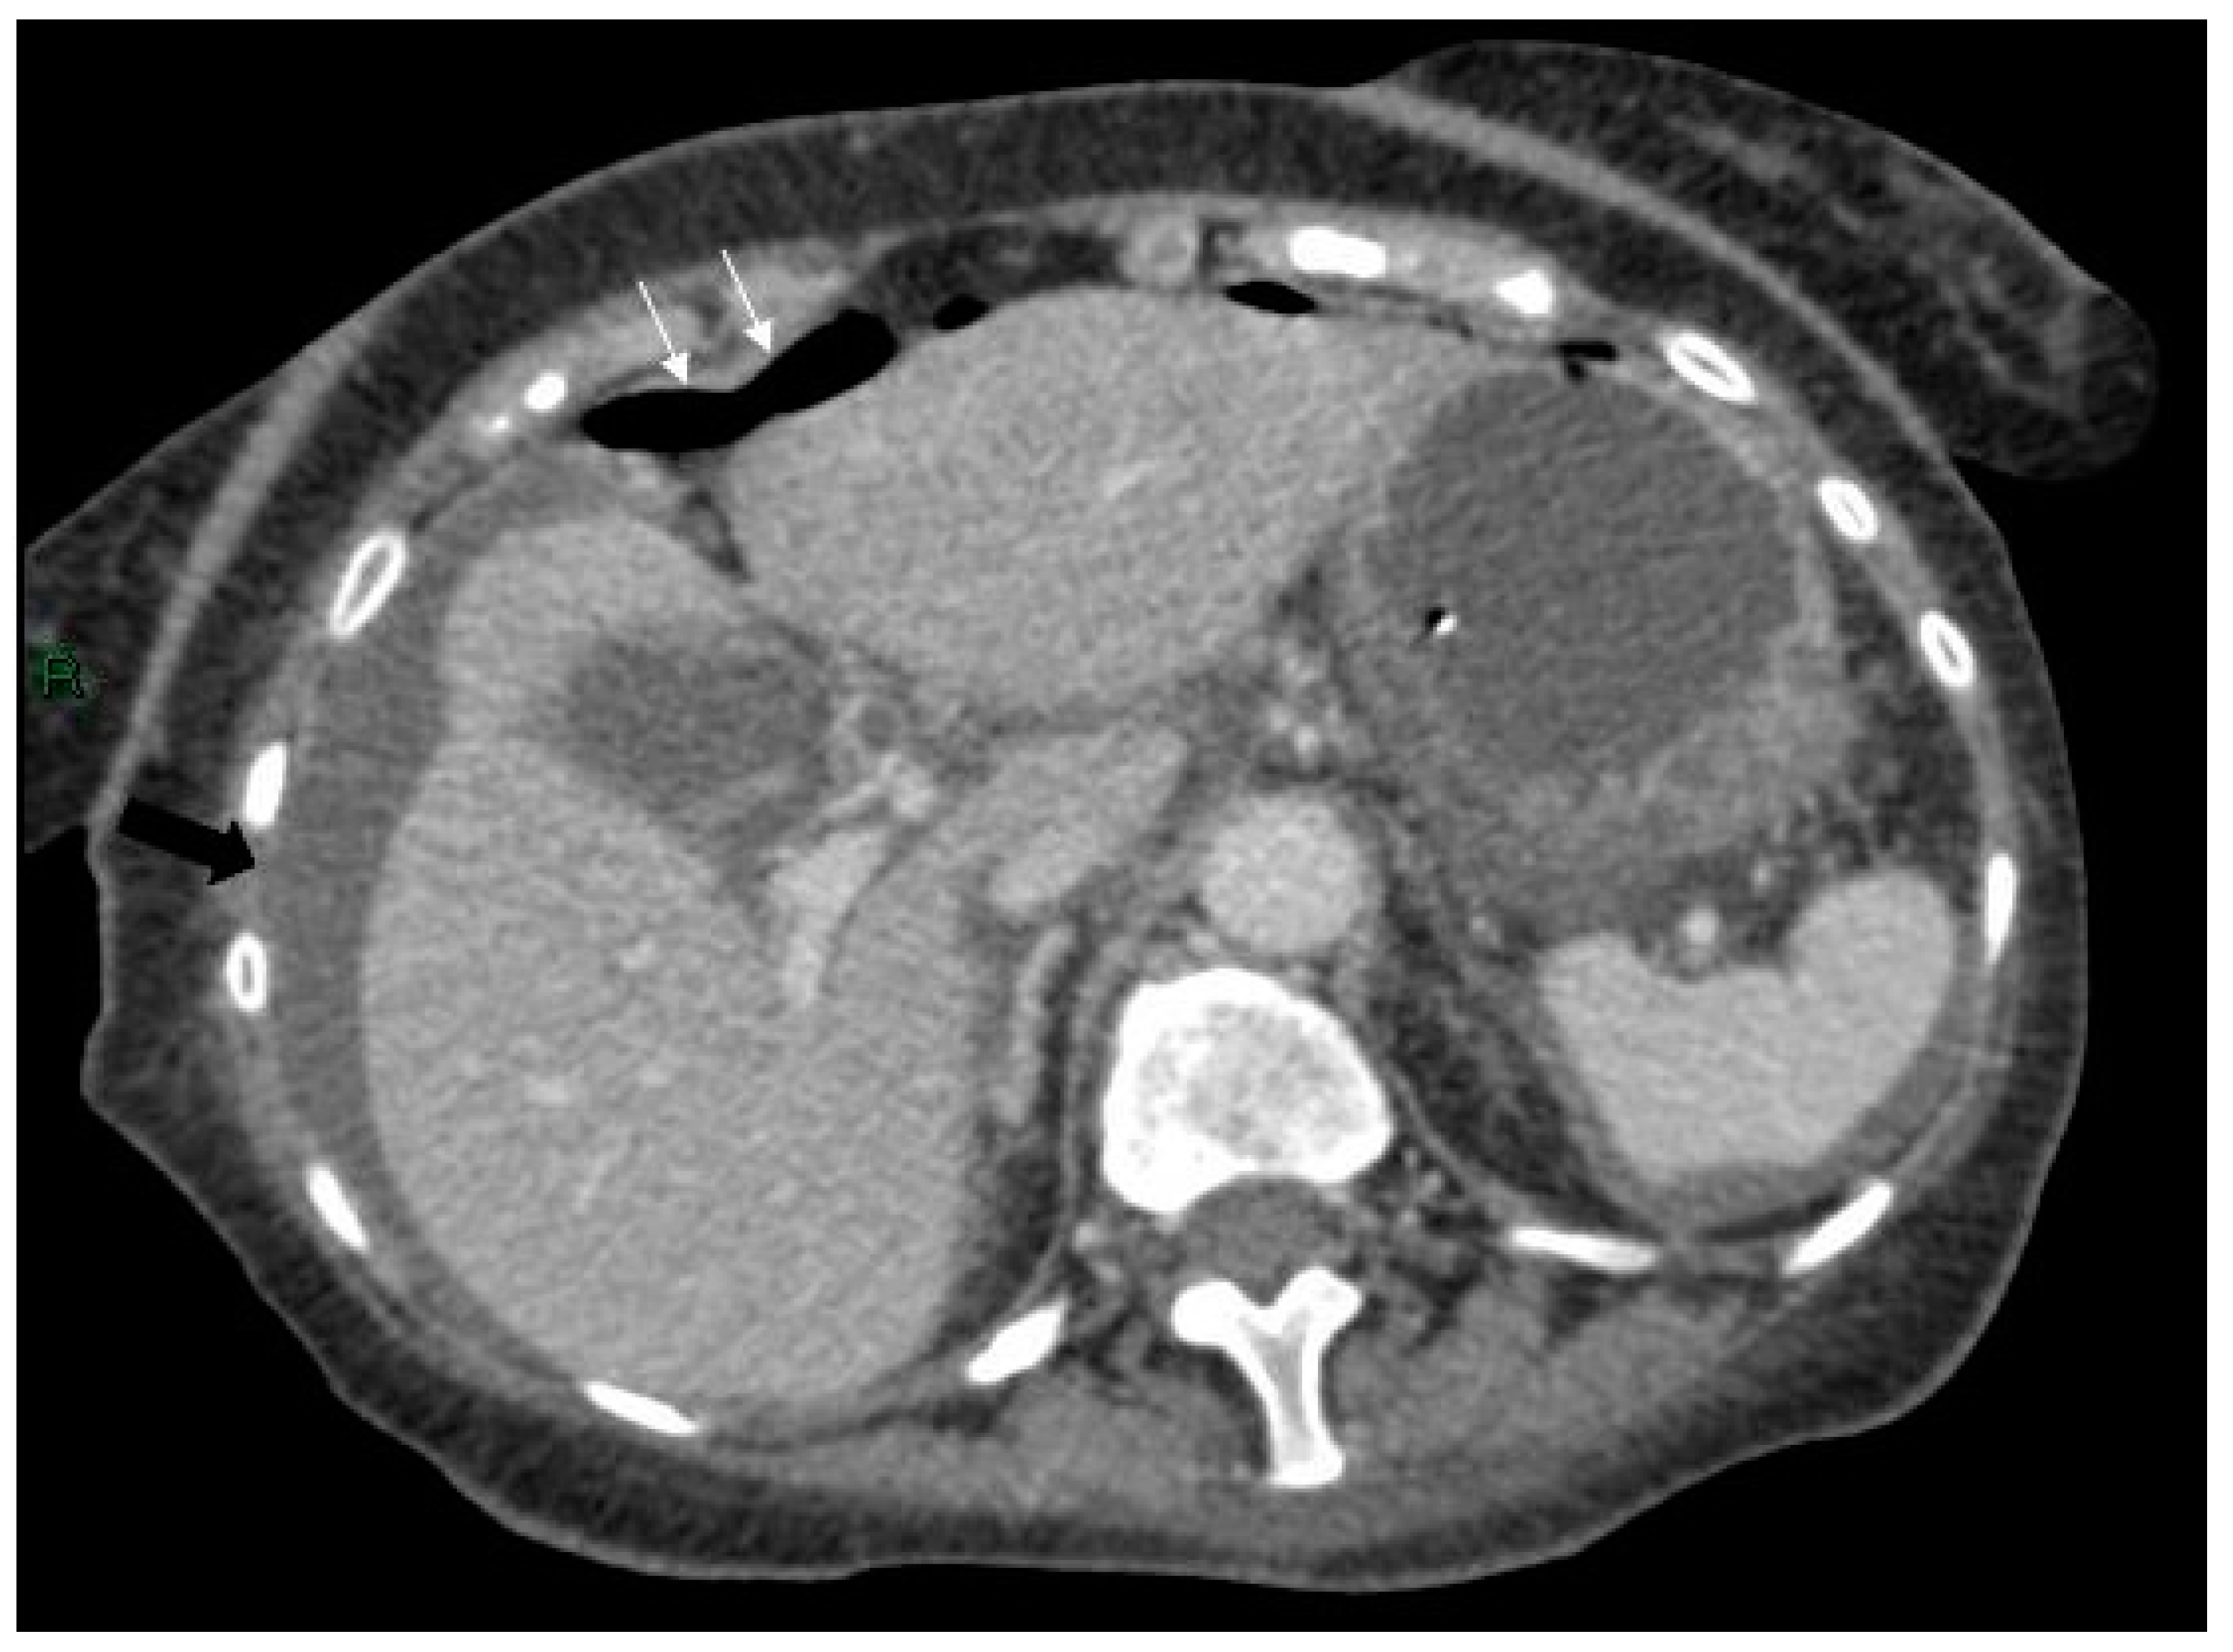

Figure 4.

Axial CT scan of abdomen showing free air anterior to the liver (white arrows) and free fluid around the liver and spleen (black arrows).

Figure 5.

Initially, Axial CT scan showing the stomach containing a nasogastric tube anterior to the cyst (large white arrow), free air (small white arrows) and inflammatory changes in the soft tissues between the stomach/duodenum and the cyst (black arrow).